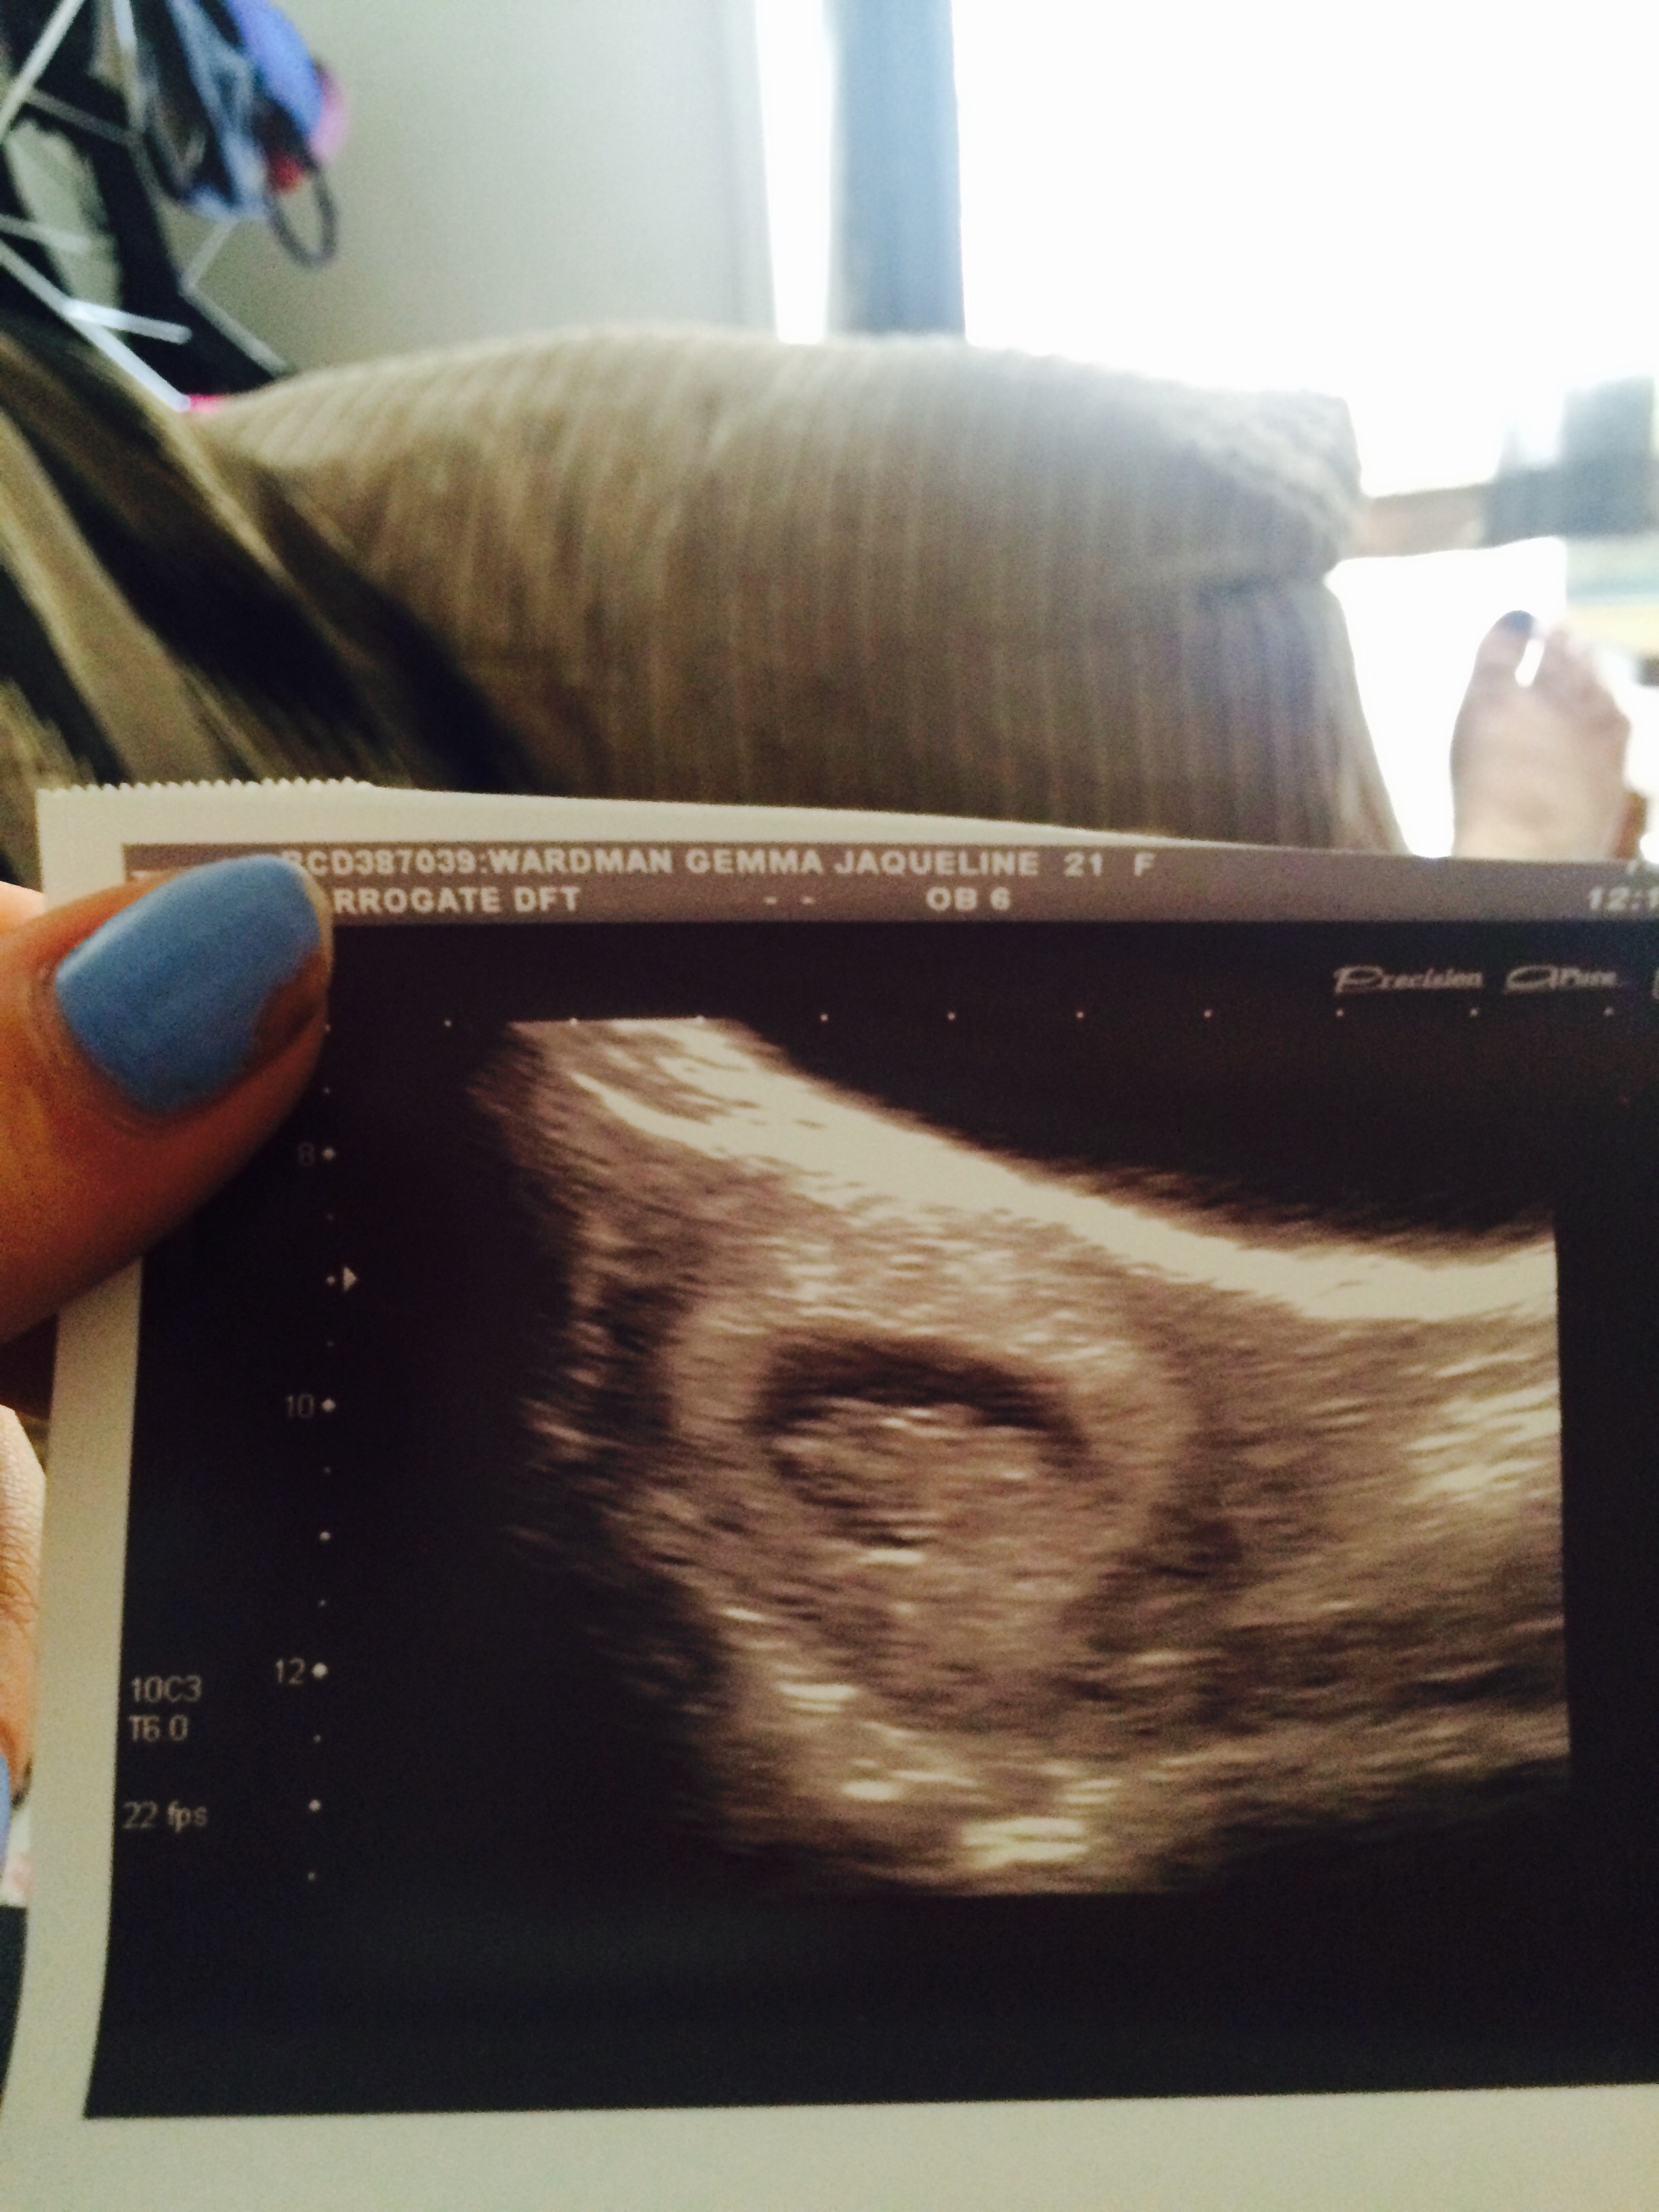

Congrats everyone ! Here's my little bean at 9 weeks got 12 week scan Wednesday very exited ! Does anyone look at their scans and think boy or girl?! Xxz

Here's my little bean at 9 weeks got 12 week scan Wednesday very exited ! Does anyone look at their scans and think boy or girl?! Xxz